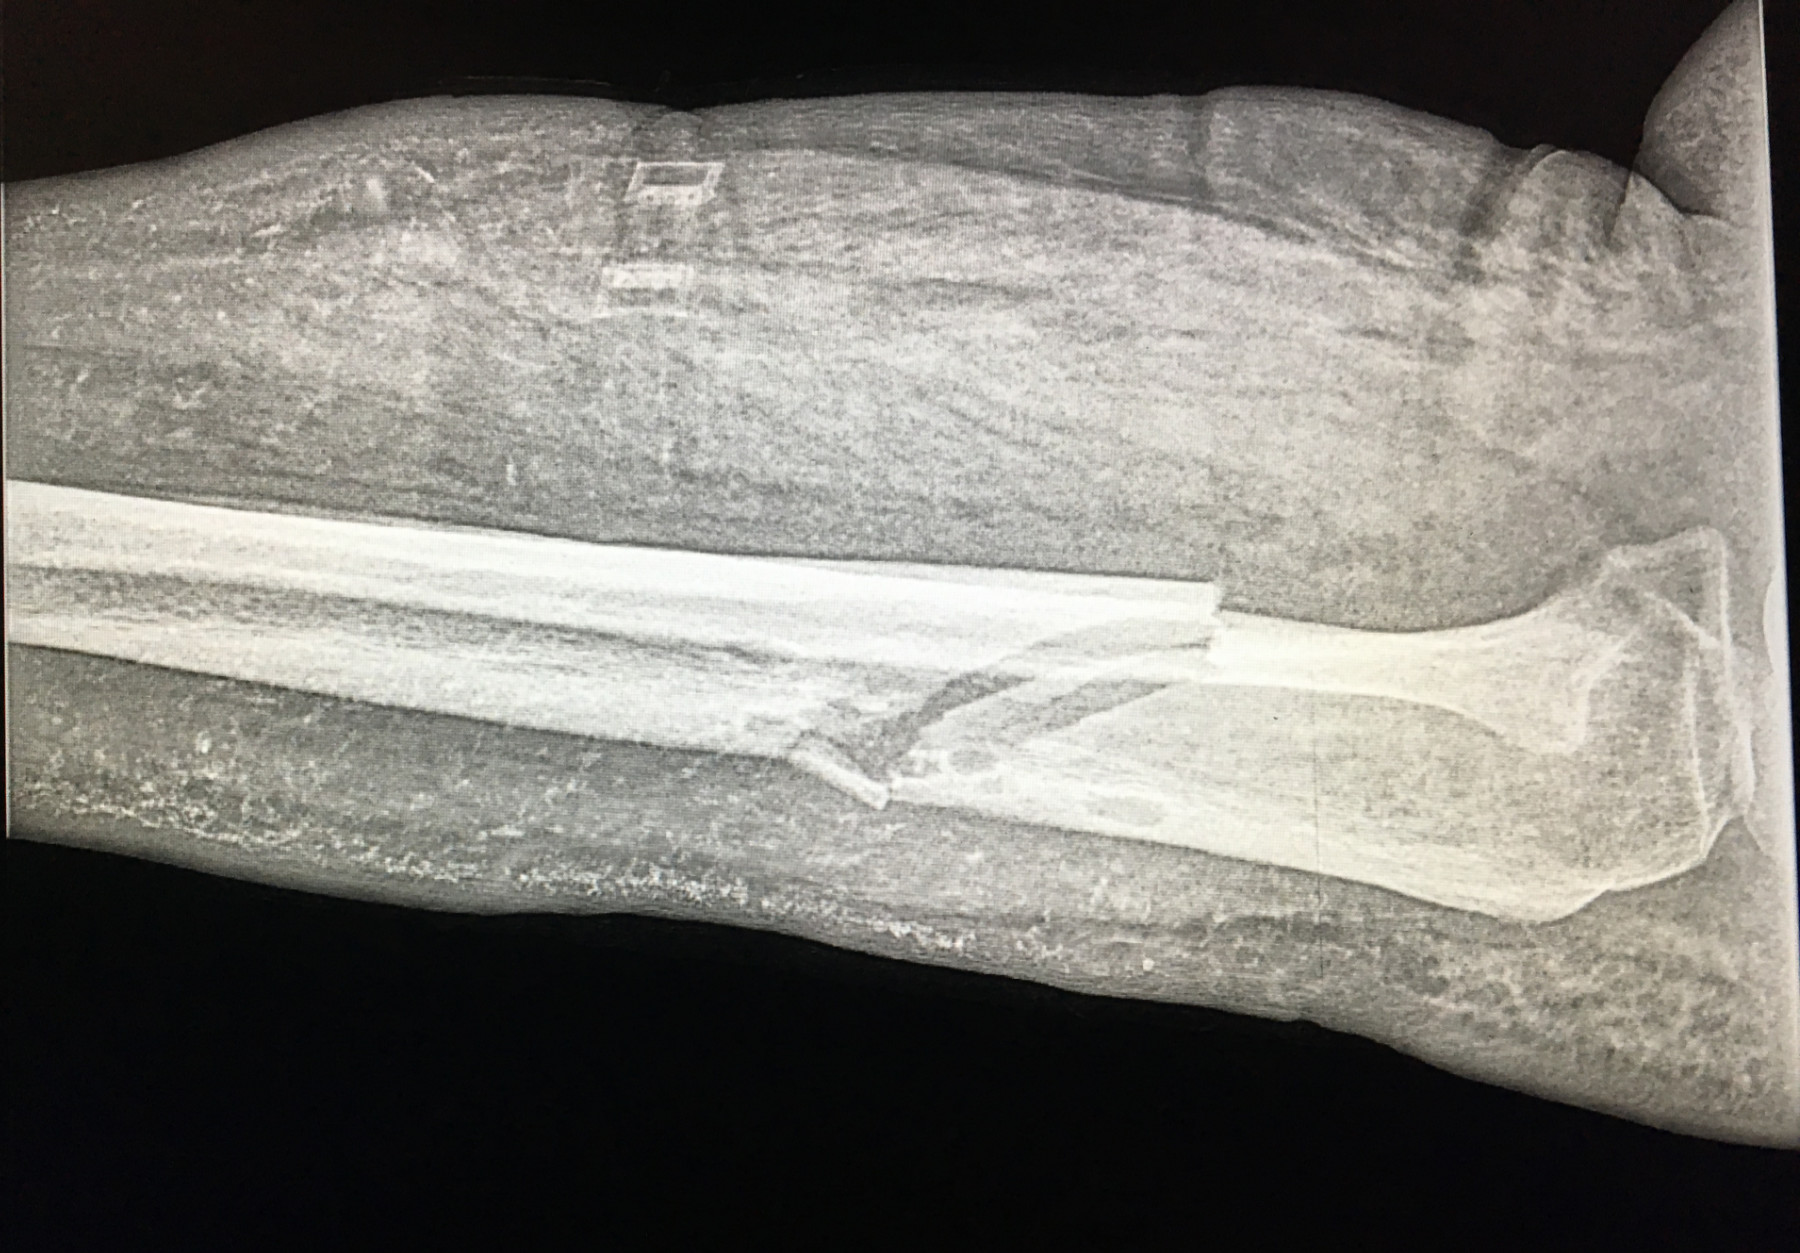

Radiología Digital como Herramienta Complementaria en el Dictamen de Bienes Muebles

Desde el descubrimiento de los rayos “X” y las placas radiográficas por Wilhelm Conrad Roentgen y su posterior difusión a través de la Asociación Físico médica de Wurzburg el 28 de diciembre de 1895, que fue la primera asociación que habló de los nuevos rayos que podían penetrar el cuerpo y fotografiar los huesos, ha habido muchos cambios tanto en la forma de obtener, procesar e incluso en la forma de visualizar, manejar y almacenar las placas radiográficas.